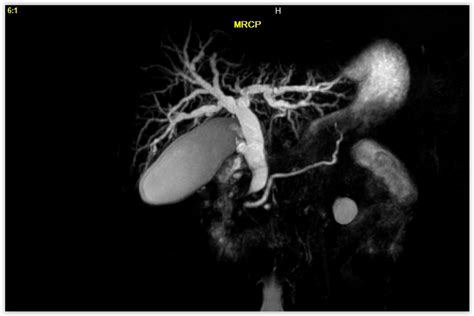

Learn what is MRCP test, a non-invasive imaging procedure using magnetic resonance cholangiopancreatography to visualize the bile ducts and pancreatic system. Discover how this diagnostic scan helps physicians detect gallstones, tumors, or blockages in the biliary tree without surgery. Get essential insights on the MRI-based scan procedure, preparation, and how it effectively identifies digestive system health issues.

Read full article: What Is Mrcp Test